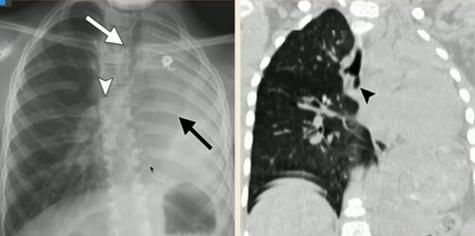

Example 1 主诉:30周早产儿出生后呼吸困难

胸片特点:气管插管;弥漫白色“铅笔尖”样白色小点。

诊断:新生儿呼吸窘迫综合症(表面活性物质缺乏症/透明膜疾病):是早产儿呼吸困难最常见的原因。

图5.新生儿呼吸窘迫综合症Example 2 主诉:足月儿剖宫产出生后出现呼吸困难

图7.新生儿B组链球菌肺炎Example4 主诉:过期产儿出生后呼吸困难

胸片特点:粗条、绳索状阴影(被阻塞的小呼吸道塌陷、不张);过度充气(未阻塞的小气道代偿性过度通气);常见并发症:肺气漏、气胸。

诊断:胎粪吸入综合征(对称性粗条线索状阴影/大片阴影)

图8.胎粪吸入综合征2